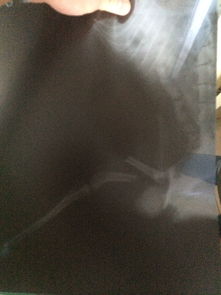

看了你追加描述和圖片,基本確定是骨折!不打算去醫院的話(huà)就按照我上面說(shuō)的做,狠狠心找到骨折的地方,試著(zhù)做一下整復,外邊用硬紙殼固定!可以去買(mǎi)一些人藥!狗狗會(huì )很快好起來(lái)的

我家狗狗一歲之前前腿骨折, 拍片和你這個(gè)情況看起來(lái)差不多. 沒(méi)有做麻醉和內固定手術(shù). 做的是外固定, 不過(guò)做好外固定以后就要注意補鈣, 一個(gè)月左右, 就好了. 平時(shí)要看好它. 不能讓它亂動(dòng), 特別是睡覺(jué)之前要確定它能正常躺下, 躺下和站起來(lái)的過(guò)程是比較痛的. 小狗的恢復能力比人強很多, 他們的代謝速度是我們的好幾倍. 所以也不需要太擔心了. 但是如果一定要做手術(shù)的話(huà), 鋼針一定要取出來(lái)的. 至于麻藥的風(fēng)險, 不能說(shuō)沒(méi)有. 我家的做絕育手術(shù)也用了全身麻醉, 有各別狗狗會(huì )有過(guò)敏性休克. 但是幾率很低.至于這個(gè)南瓜子,我沒(méi)有喂過(guò). 不過(guò)如果是我要喂狗狗吃的話(huà), 應該會(huì )磨碎或者弄小顆拌狗糧, 它就會(huì )吃. 我家的是吃貨, 不挑食的. 假如挑食的話(huà), 可以稍微烤一下嘛, 香一點(diǎn)自然會(huì )吃啦! 其實(shí)狗狗真的好的很快的. 最主要的是看好它不要讓它亂動(dòng)重復受傷, 如果接好了以后固定住了又錯位, 就很麻煩了. 還有接不好或者又亂動(dòng)錯位了還給長(cháng)好了, 就很可能變成長(cháng)短腿或者Z型腿. 如果對你有幫助記得采納哦。